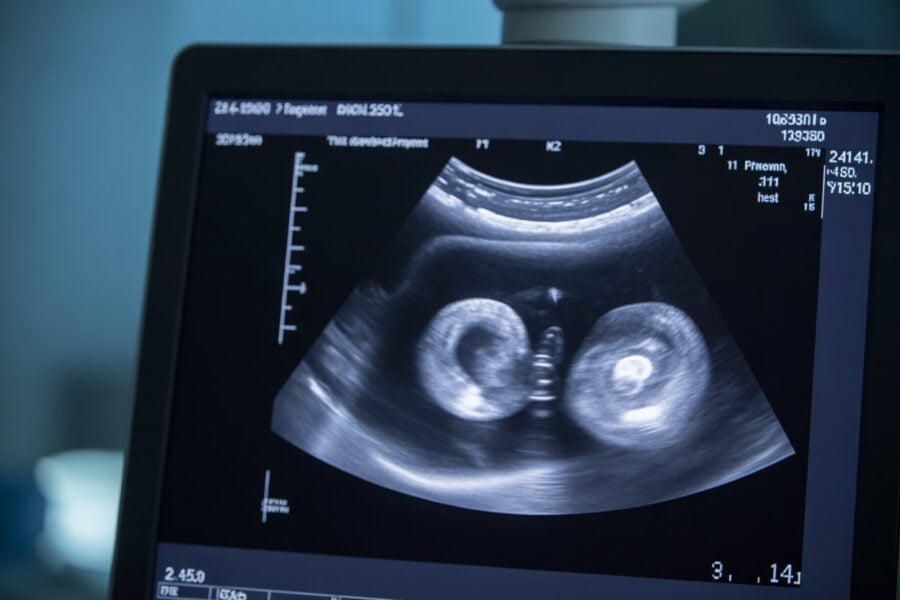

(Of course i didn’t know it was twins yet lol).

A few minutes into the scan, the midwife smiled and said, “You’re going to be busy… you’re having twins!”

After the twin reveal, the midwife started pointing out every little body part on the screen: head, legs, arms, hands… all the details.

I’ll be honest, I could barely see any of it.

Well, the heads I could spot. The legs were maybe visible. But the feet or toes? No chance.